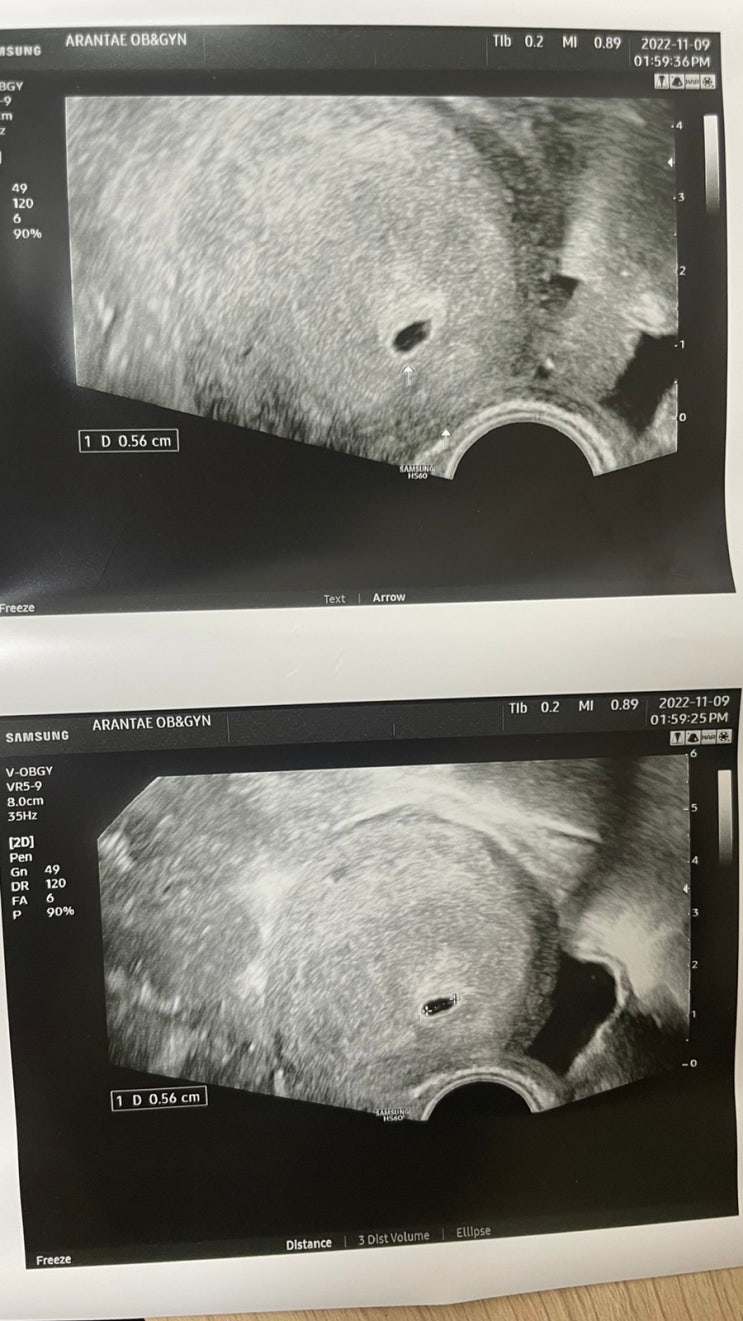

임신 5-6주차 증상, 심장소리, 입덧시작, 출산 예정일 수정

이 블로그를 쓰고있는 지금. 6주 4일차, 입덧인지 쳇기인지 모르겠지만 속이 매우 불편하여 끝없이 일부러 ...